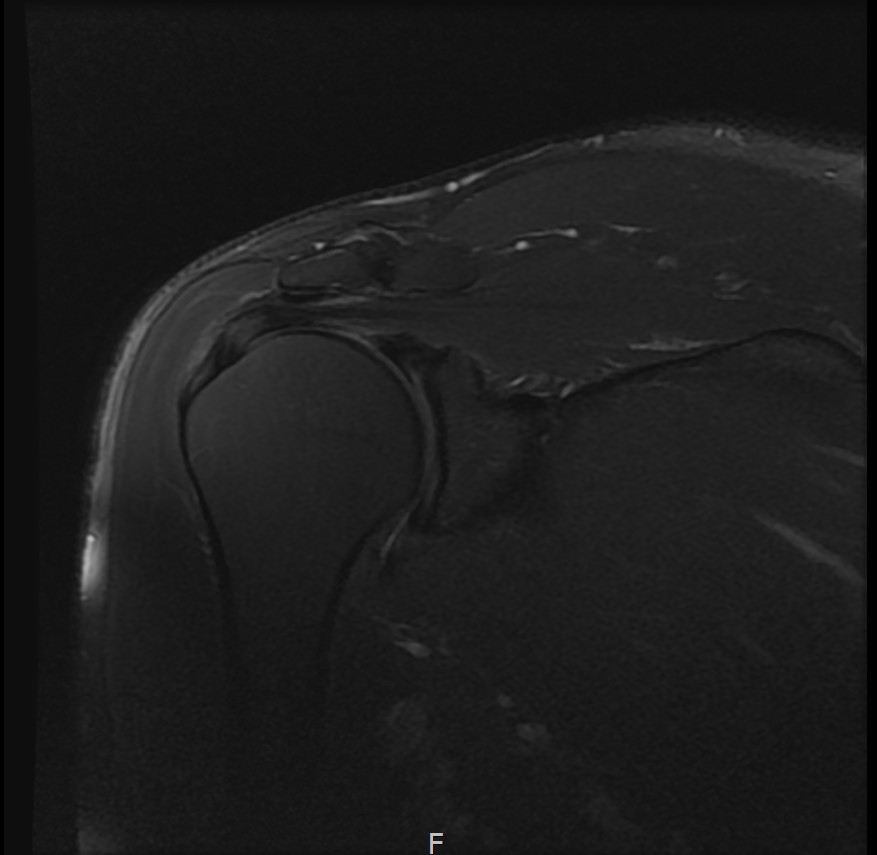

MRI를 검토해보았습니다.

회전근개 극상건의 점액낭면측(bursal-side) 부분파열. 처음보다 파열 범위가 약간 넓어져 있었고, 인대가 얇아진 소견도 보였습니다.

6개월 후 MRI로 인대 두께 확인

6개월 후 MRI: 인대 두께 5.8mm (1.6mm 증가)

6개월 후 MRI: 인대 두께 6.2mm (1.7mm 증가)